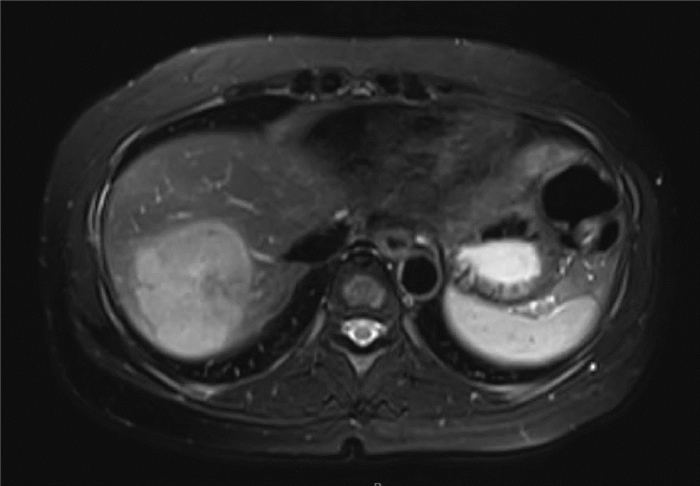

Clinical and pathological features of progressive familial intrahepatic cholestasis type 3

Yuhang WENG, Qingfang XIONG, Duxian LIU, Xulei ZHANG, Yongfeng YANG

2022, 38(1): 154-159. DOI: 10.3969/j.issn.1001-5256.2022.01.024

Abstract(1841) HTML (764) PDF (2621KB)(137)

Abstract:

Objective  To investigate the clinical and pathological features of progressive familial intrahepatic cholestasis type 3 (PFIC3).  Methods  A retrospective analysis was performed for 1326 patients with unexplained liver disease who attended Nanjing Second Hospital from January 2017 to December 2019, among whom 8 patients were diagnosed with PFIC3 based on clinical/pathological manifestation and gene sequencing results (1 patient did not undergo liver biopsy due to contraindication). Clinical, laboratory, imaging, and pathological findings were analyzed and a literature review was performed for the pathology of ABCB4-related diseases to summarize the clinical and pathological features of PFIC-3.  Results  Among the 8 patients with PFIC3, there were 5 male patients and 3 female patients, with a median age of 29.5 years. Of all 8 patients, 4 (50%) manifested as chronic cholestasis and 4 (50%) manifested as biliary cirrhosis, among whom 3 (75%) had the manifestation of portal hypertension. As for biochemical examination, 75% (6/8) had an increase in alkaline phosphatase, and 100% (8/8) had an increase in gamma-glutamyl transpeptidase. As for imaging examination, 50% (4/8) had cholecystitis, 25% (2/8) had gallstones, 25% (2/8) had bile duct dilatation, 75% (6/8) had splenomegaly, and 25% (2/8) had liver cirrhosis. As for liver biopsy, all 7 patients manifested as bile duct injury and/or reduction, and 57.1% (5/7) had absence of the bile duct. Multidrug resistance P-glycoprotein 3 (MDR3) immunohistochemical staining showed normal expression in 42.9% (3/7) of the patients and reduced expression in 57.1% (4/7) of the patients. Literature review obtained 17 articles with a description of the bile duct or MDR3 immunohistochemistry. Among the 7 patients with low phospholipid-associated cholelithiasis, 71.4% (5/7) had normal bile duct, 14.3% (1/7) had bile duct reduction, and 14.3% (1/7) had absence of the bile duct; among the 6 patients with intrahepatic cholestasis of pregnancy, 16.7% (1/6) had normal bile duct, 50% (3/6) had bile duct reduction, and 33.3% (2/6) had absence of the bile duct; among the 8 patients with PFIC3, 25% (2/8) had bile duct reduction and 75% (6/8) had absence of bile duct; among the 21 patients with PFIC3, 9.5% (2/21) had normal expression of MDR3, 23.8% (5/21) had a reduction in the expression of MDR3, and 66.7% (14/21) had absence of the expression of MDR3.  Conclusion  PFIC3 mainly manifests as cholestasis, cholelithiasis, and hepatic fibrosis. Pathological manifestation includes bile duct injury and bile duct reduction or absence of the bile duct in severe cases, and the degree of injury is associated with disease severity. MDR3 immunohistochemistry may show normal expression, reduced expression, or absence of expression, and diagnosis cannot be excluded in patients with normal expression. Genetic testing can be performed for diagnosis when necessary.